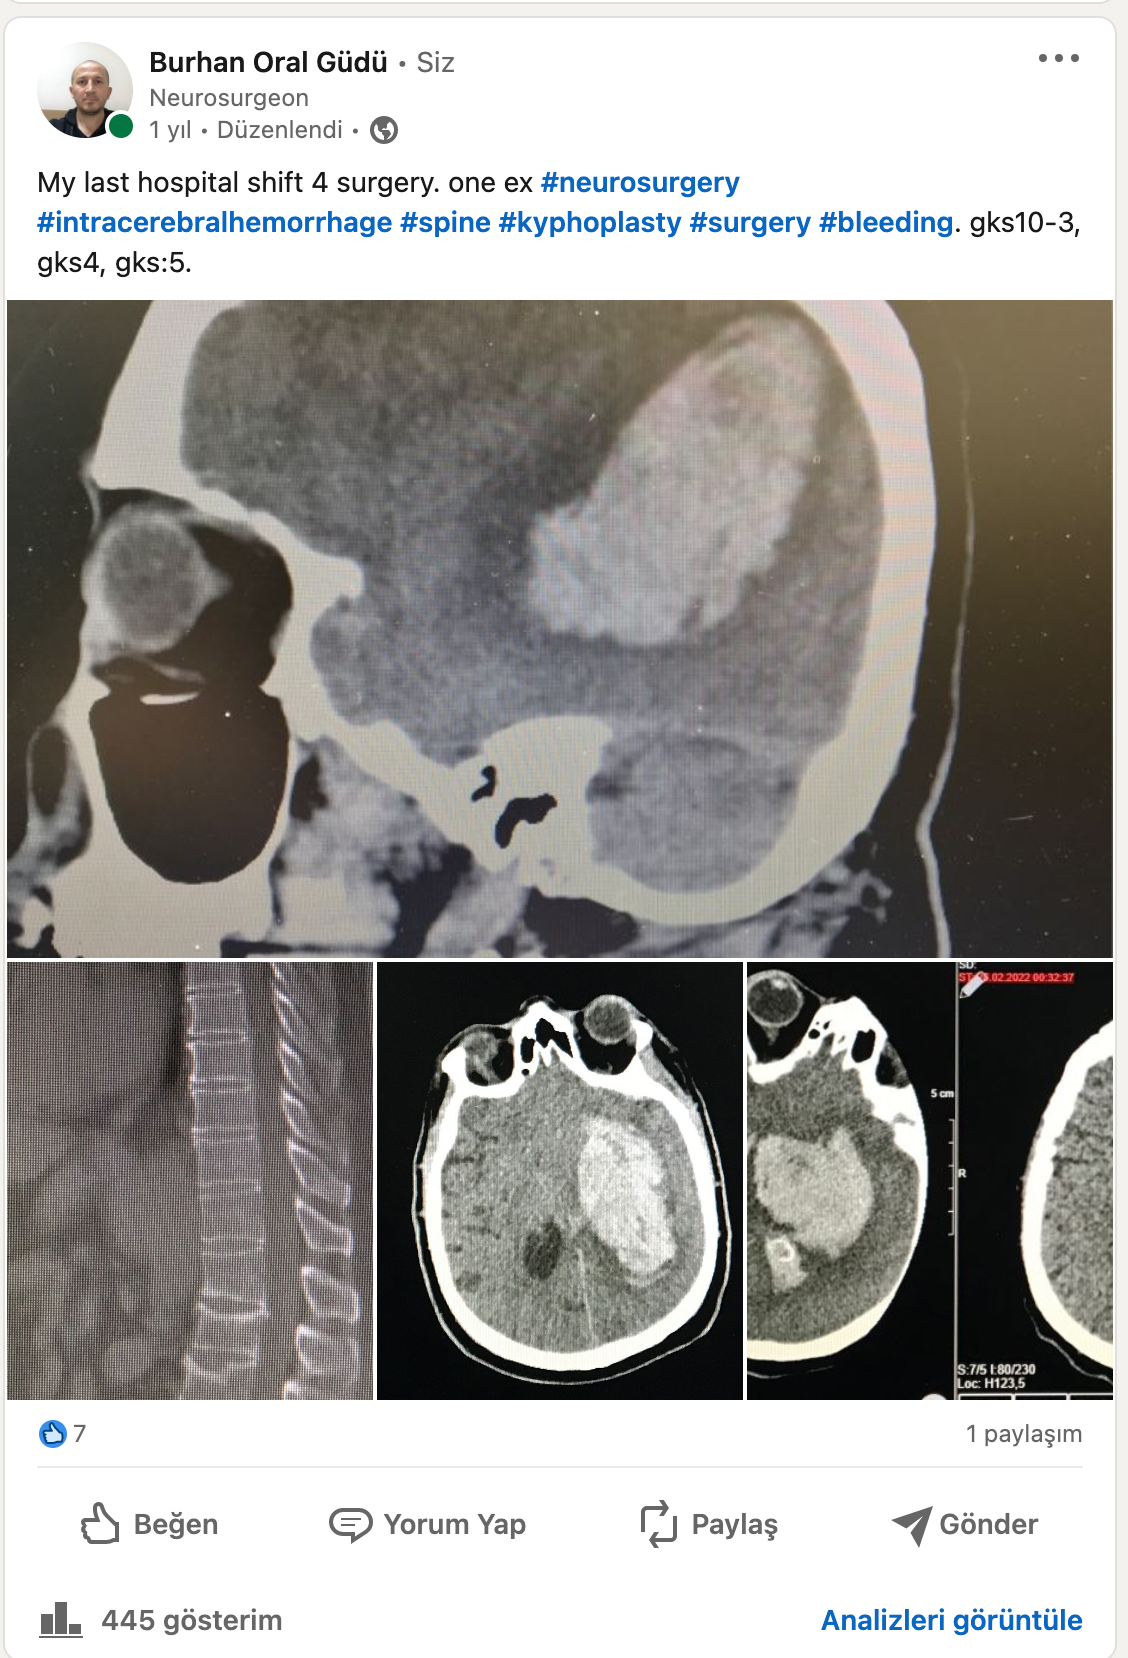

Kifoplasti - Vertebroplasti Nedir